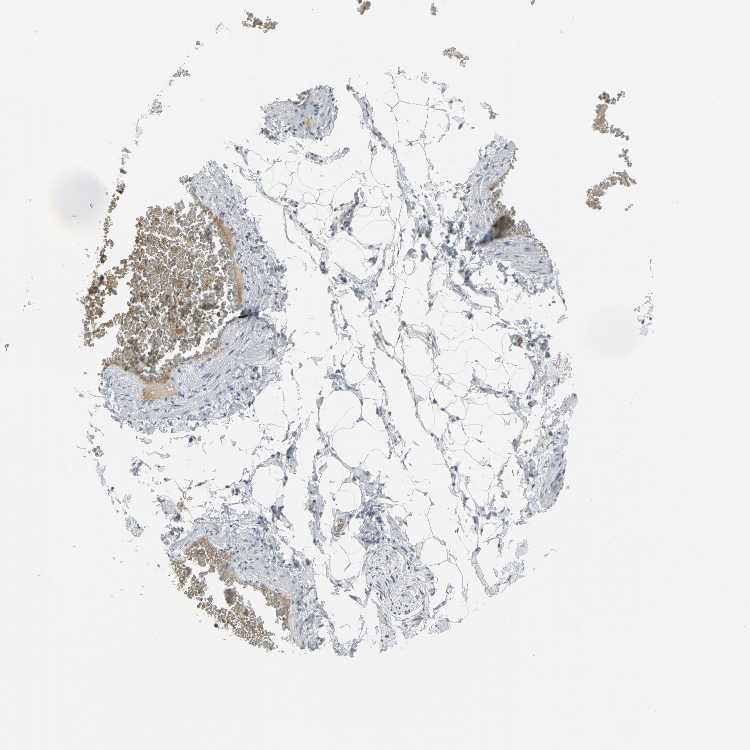

SOFT TISSUE 1 - Antibody stainingi

Antibody staining in the annotated cell types in the current human tissue is reported as not detected, low, medium, or high, based on conventional immunohistochemistry profiling in selected tissues. This score is based on the combination of the staining intensity and fraction of stained cells.

Each image is clickable and will lead to virtual microscopy that enables deeper exploration of all samples and also displays staining intensity scores, fraction scores and subcellular localization as well as patient and tissue information for each sample.

Antibody HPA004098

Chondrocytes Not detected

Fibroblasts Not detected

Peripheral nerve Not detected